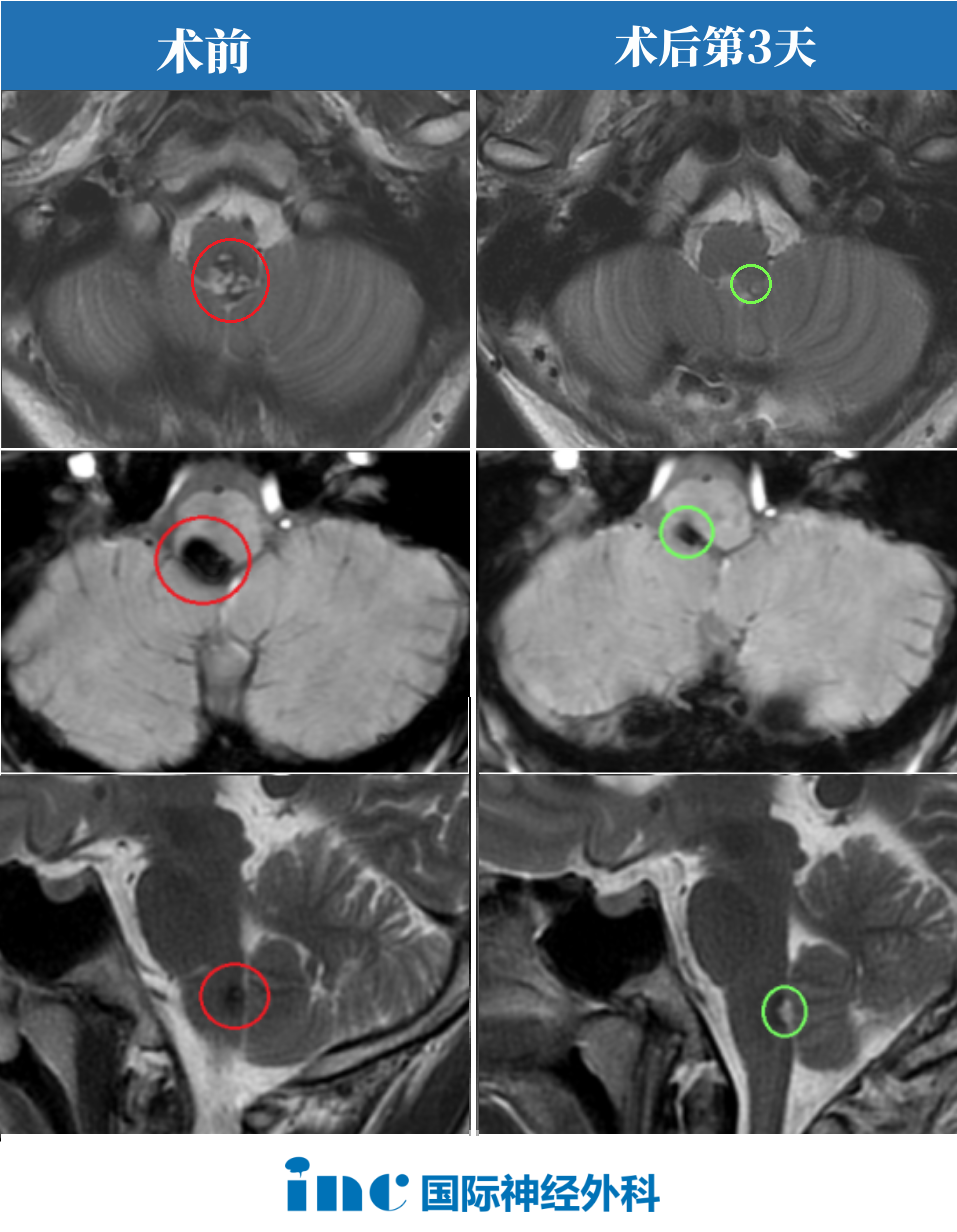

术前情况:20岁,大学生,意识紊乱并逐渐恶化,左偏瘫,MRI显示脑干中脑出血,急性梗阻性脑积水。病变位于脑干腹侧中脑中线,体积为10.7立方毫米,深度为42.5mm和和11.6°的肿瘤侧倾角(图A、B)。

手术入路:巴特朗菲教授根据患者的病情和肿瘤生长及MRI影像特点,先行脑室引流术,后采用双额骨瓣开颅、经基底纵裂入路进行病变全切手术。

术后情况:术后Maritta的恢复也很顺利。患者的意识和偏瘫迅速改善,脑积水消退。病人步行出院,没有3个月后随访的神经或认知功能障碍。术后MRI显示完全切除了轴内血肿和血管病变(图C、D)。

图A和B显示术前MRI影像,出血性中脑海绵状血管瘤诊断明确。黄色虚线表示肿瘤深度(42.5毫米)。图C、D显示完全切除血管病变后的术后MRI,病变全切,压迫占位效应解除,脑组织复位,未见手术损伤如脑出血、脑水肿等。